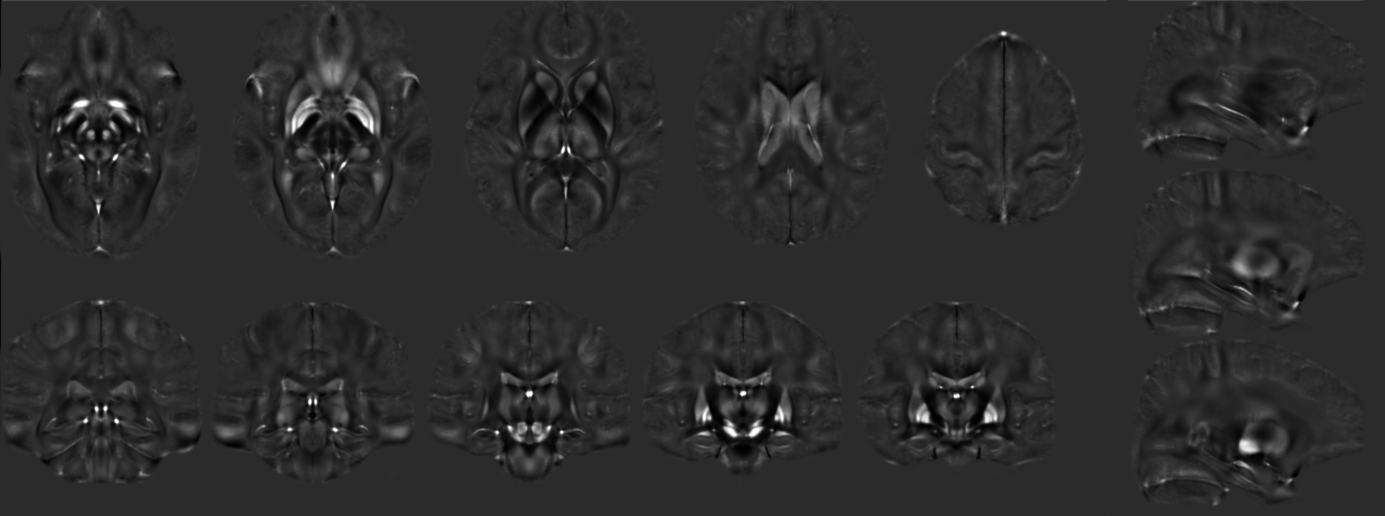

GRE and QSM average 7T model

GRE model

greModel_L14_gre-7T-weightedMeanOfAllEchoes-asym-mincanon_v0.8 [  View model online  | Download mnc (517 MB) | Download nii (647 MB) ]

QSM model

qsmModel_L14_gre-7T-weightedMeanOfAllEchoes-asym-mincanon_v0.8 [  View model online  |  Download mnc (168 MB) | Download nii (647 MB) ]

QSM: 29 (14 female, 26.6±3.8yr) individuals were imaged using a multiple echo gradient recalled echo 3D whole brain dataset. TR=25ms, TE=4.4,7.25,10.2,13.25,16.4, 19.65,23ms flip angle=13, FOV 210x181.5x120mm, matrix=280x242x160, GRAPPA=2. The phase data was combined using COMPOSER [8] and susceptibility processing was performed using total generalized variation (TGV) [9], which incorporates phase unwrapping, background field removal and dipole inversion in a single step.